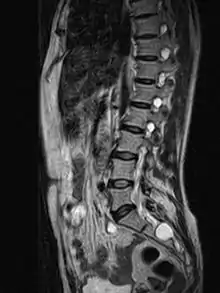

MRI

MRI, or Magnetic Resonance Imaging, is considered the imaging study of choice in identifying Tarlov cysts. MRI provides better resolution of tissue density, absence of bone interference, multiplanar capabilities, and is noninvasive. Plain films may show bony erosion of the spinal canal or of the sacral foramina. On MRI pictures, the signal is the same as the CSF one.